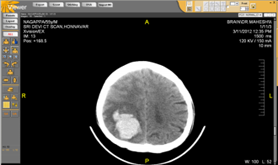

CT of the brain can be done with or without contrast, but it is not necessarily required. CT scanning of the brain is done in cases of bleeding, brain injury and skull fracture as well as for cerebral aneurysms. Even in cases of enlarged brain in patients with hydrocephalus this unique imaging technology is very helpful. The other medical symptoms for which this scan is called for could be anything from a headache, weekness, seizure, confusion, etc.